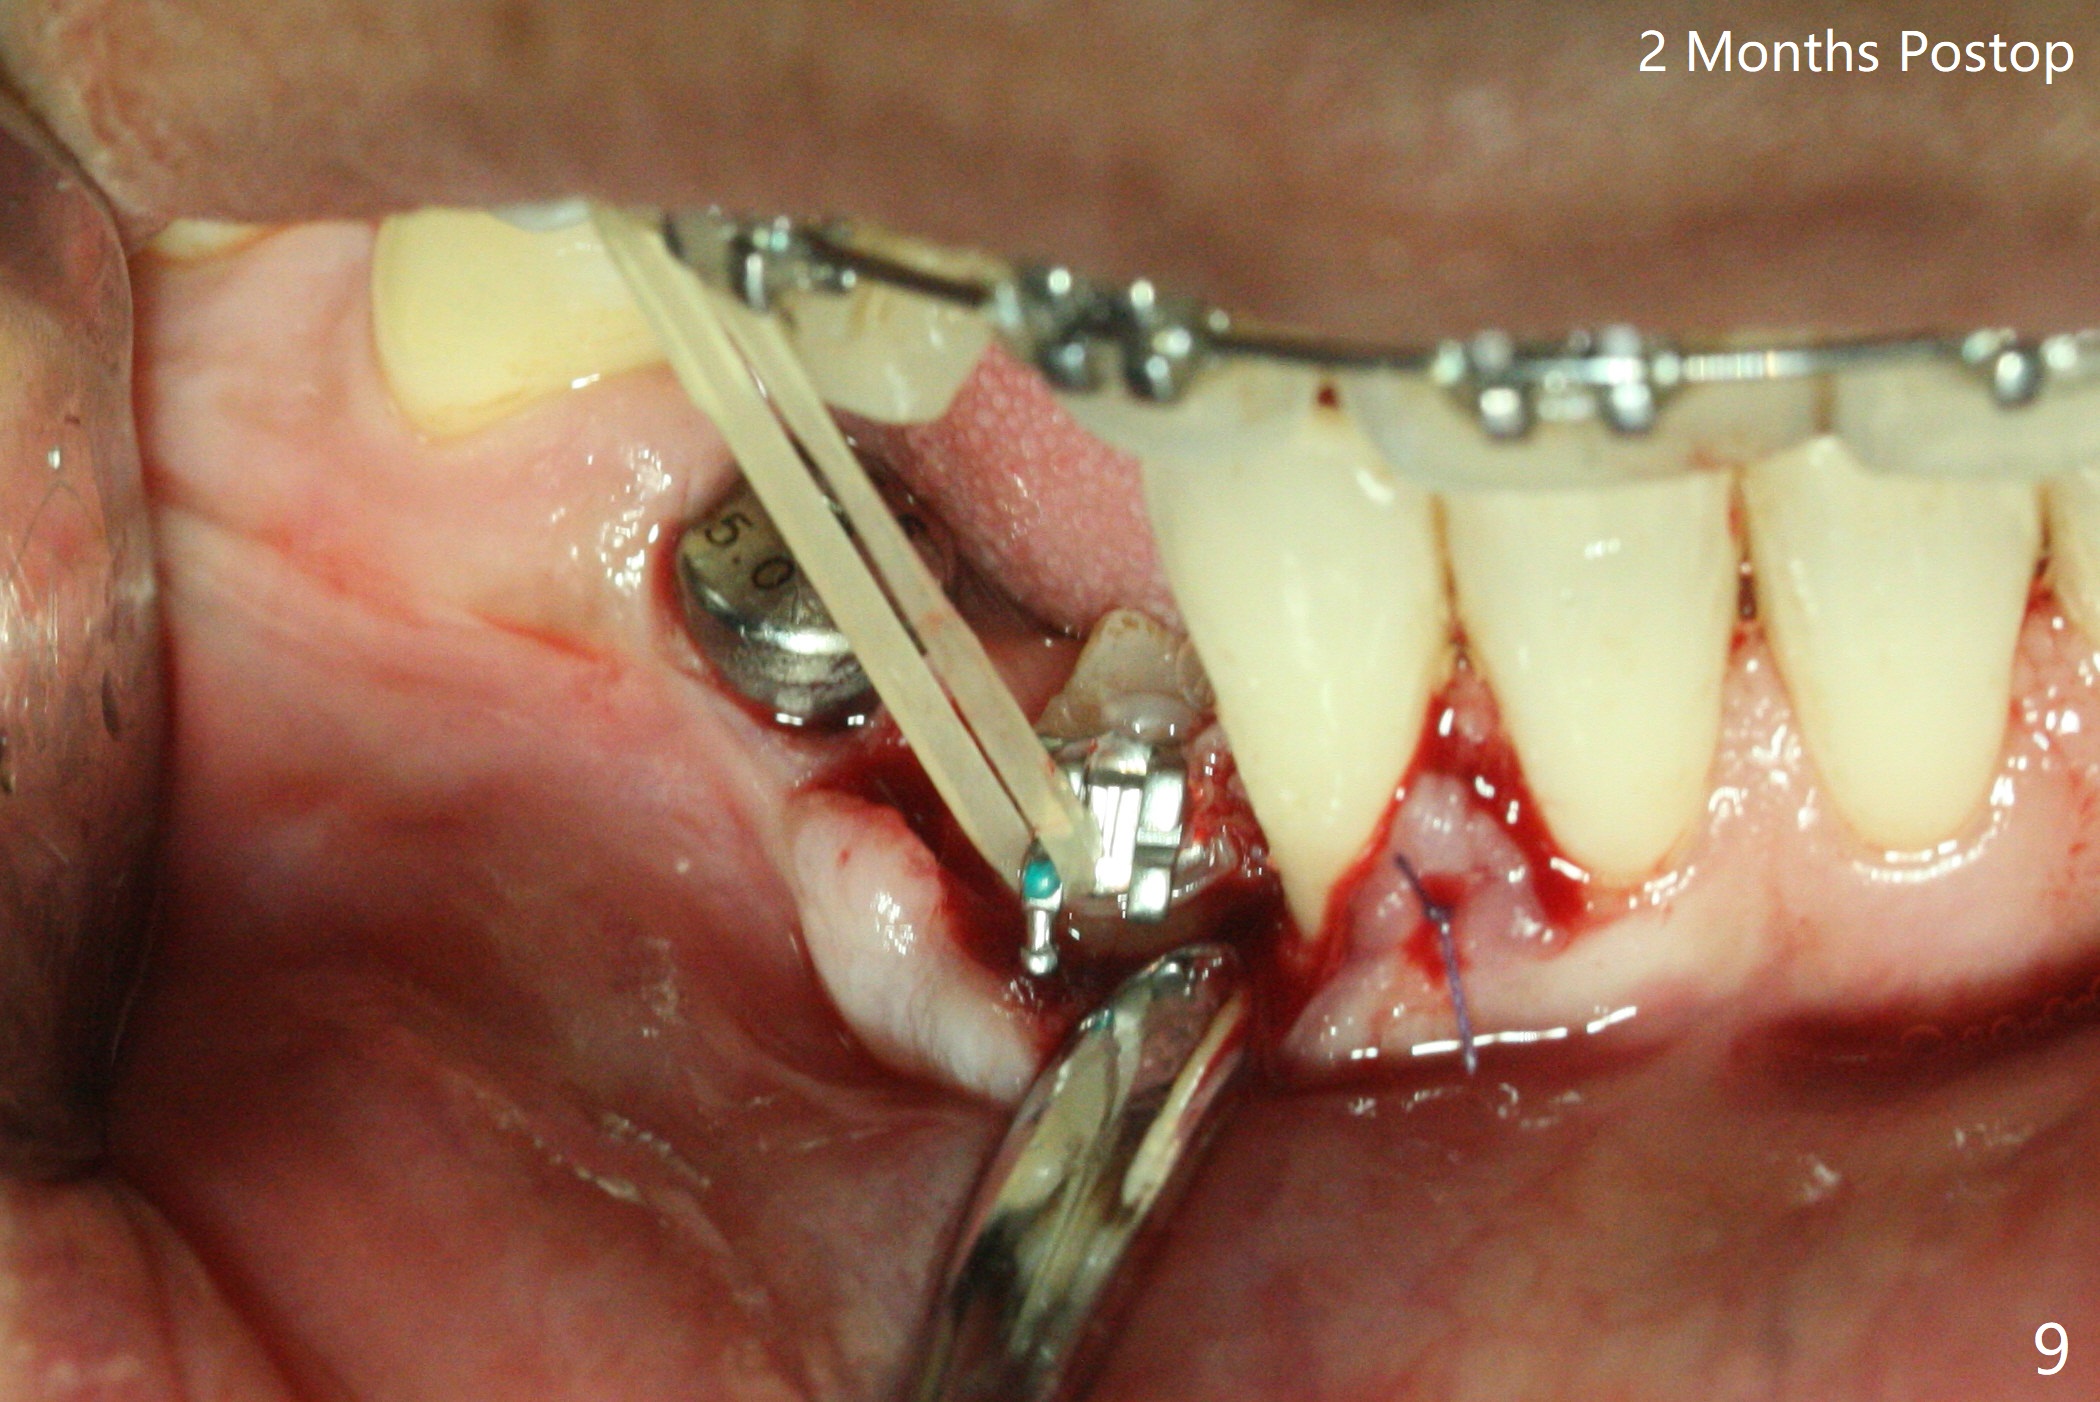

When the surgical guide for #28 is removed, the 4x13 mm implant is found to be superficial and buccal. Part of the buccal mucosa is nonkeratinized. After 1 mm deeper placement of the implant, CT confirms the buccal placement (Fig.1, as compared to design). In fact the guide was doubly checked for fitness prior to osteotomy, but grossly it seemed to be seated properly. The suspicion is related to the trimming at the site of #27 (Fig.2,3 (*), as compared to a mounted model in Fig.4,5 (arrowhead) and the model sent to lab for guide fabrication). The lab agrees to redesign the case. There is a narrow buccal band 1 week postop (Fig.6). The patient is a smoker. The implant was placed buccal (Fig.7, 1 month postop). A new 4x13 mm implant is placed on the top of the 1st line following 3x14.5 mm drill (Fig.8 (35 Ncm)). In fact the implant position is not changed much. Four months post banding (20 ss) and 2 months post 2nd implant placement, the tooth #27 is exposed for bracket; extrusion is initiated (Fig.9). In 3 weeks of retraction, the bracket is supragingival (Fig.10). The canine contacts the distal healing abutment with 2 months of retraction (Fig.11). It seems necessary to initiate lower bracket placement. There is no bone loss 4 months postop (Fig.12). A 4.5x7(4) mm abutment is placed (Fig.13) for a temporary crown as an anchor (Fig.14) to further extrude #27 with continuous inter-arch retraction (to reduce tension upon #26 with severe bone loss (Fig.12)). LR3 extrusion is incomplete, although there is an increase in bone distal to LR2 ~ 10 months of extrusion (Fig.15).